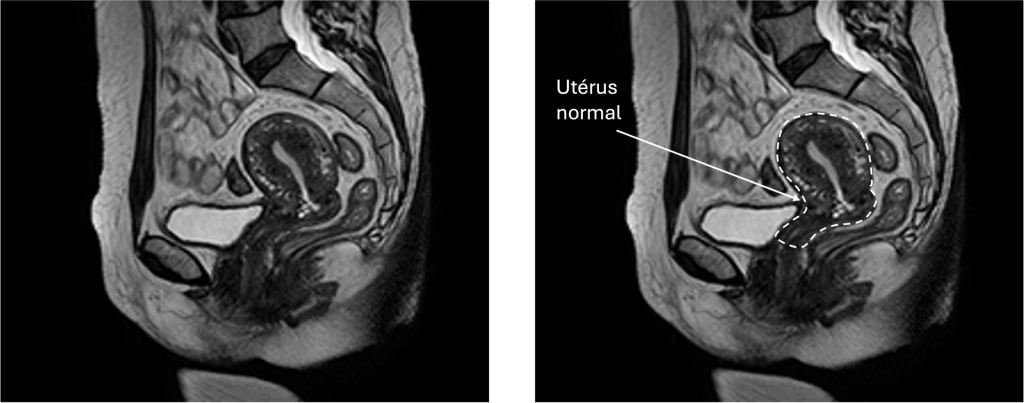

L’IRM pelvienne (Imagerie par Résonance Magnétique)

L’IRM est l’examen de référence, parfois prescrite lorsque les fibromes sont nombreux, volumineux ou difficiles à localiser précisément. Elle permet une vision très précise de l’utérus et de ses structures. Elle est particulièrement utile avant une intervention ou pour différencier un fibrome d’une autre anomalie comme l’adénomyose ou les varices pelviennes.

Les fibromes peuvent entrainer une augmentation de taille de l’utérus.

Chaque femme peut avoir un seul fibrome ou plusieurs, de types différents. Le diagnostic se fait généralement par échographie ou IRM, selon la situation.